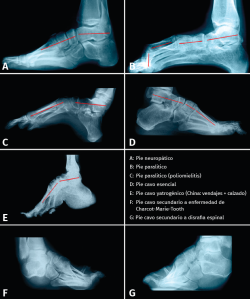

El punto de rotura de la línea de Meary se encuentra en los pies cavos esenciales y en los pies cavos que vemos en los deportistas y bailarines al nivel de la articulación naviculocuneana; en los pies cavos de origen paralítico o neuropático va a depender de los grupos musculares afectados, por lo que las deformidades serán el resultado de los desequilibrios musculares que se produzcan.

Las alteraciones tridimensionales en el pie cavo son muy variables, lo que condiciona formas clínicas muy diversas. No tiene nada que ver, ni desde un punto de vista clínico ni radiológico, el aspecto de un pie cavo hipertónico de un deportista con el que presenta un pie neurológico con marcado varo de talón, o un pie cavo secundario a una secuela de poliomielitis o a una enfermedad de Charcot-Marie-Tooth. Por ello, es muy difícil asegurar que existe o no una alteración en la forma del primer CM la primera cuña o en qué articulación se produce la rotura de la línea de Meary (Figuras 6A y 6B).

Figura 6. Rotura de la línea de Meary en diferentes tipos de pie cavo (A, B, C, D y E), en los que puede observarse una gran variabilidad de la misma. En F y G, debido a la alteración tridimensional, es difícil trazar la línea de Meary.